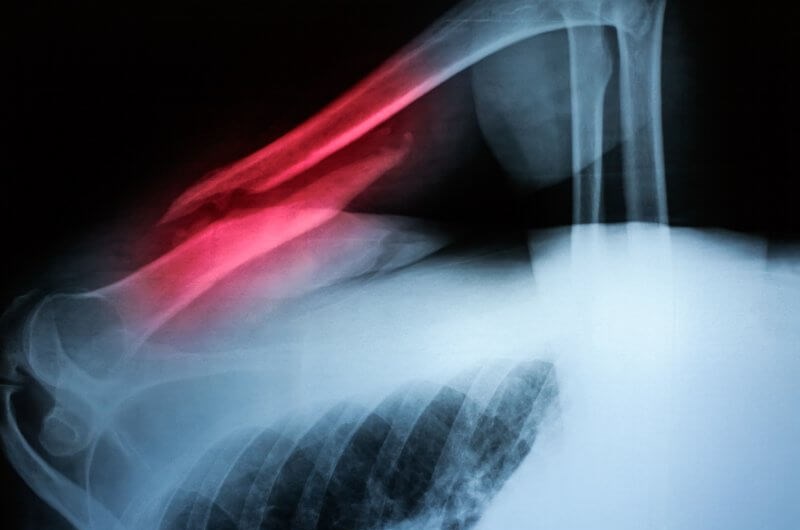

Staw rzekomy jest formą nienaturalnego połączenia między kośćmi imitującego funkcje prawdziwego stawu. Występuje on zazwyczaj w wyniku braku zrostu złamanej kości, gdy w miejscu złamania tworzy się ruchoma przestrzeń przypominająca staw. Staw rzekomy może powodować ból i zaburzenie funkcji kończyny a jego leczenie często wymaga interwencji chirurgicznej.